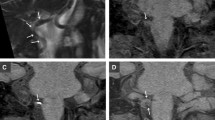

Both 3D-BB-T1WI and MRA allowed visualization of the VA of interest in arbitrary orientations, including oblique short-axis and long-axis views. As a result, 3D-BB-T1WI revealed the characteristic crescent shape of an intramural haematoma in 14 cases (87.5 %), whereas SE-T1WI and MRA revealed a crescent configuration in 7 cases (43.8 %, p < 0.0167) and 8 cases (50 %, p = 0.031), respectively (Fig. 1).

Case 4. A 41-year-old man with sudden occipital headache. MRI was obtained 20 days after onset. In serial axial reformatted images of 3D-BB-T1WI (a, b), a high-intensity intramural haematoma of the left VA is clearly shown on both slices. In the caudal slice (b), the haematoma exhibits a characteristic crescent shape (arrow). In SE-T1WI (c), a high-signal haematoma is shown in the left VA. In MRA (d), the intramural haematoma is indistinguishable from the lumen (arrow)

This study investigated the efficacy of 3D-BB-T1WI for assessing intramural haematomas in intracranial VADs. Visualization grading scores of the intramural haematomas on 3D-BB-T1WI were highest among the different sequences, and were significantly higher than those of MRA, although no statistically significant difference was observed for the haematoma detection rate. Unlike SE-T1WI, 3D-BB-T1WI has a higher craniocaudal spatial resolution (0.67 mm) and allows visualization of the VAs in arbitrary orientations. The capability to create obliquely reformatted images enabled visualization of short-axis images of the VAs and the characteristic crescent shape of an intramural haematoma in 14 cases (Fig. 1). In contrast, SE-T1WI is subject to the partial volume effect due to lower craniocaudal resolution (4.5–6mm); therefore, it can be difficult to assess small haematomas using this conventional 2D technique. SE-T1WI could reveal the typical crescent shape of the haematoma in only seven cases.

The MRA used in this study also had a high craniocaudal spatial resolution of 0.6 to 0.65 mm. However, intramural haematomas were entirely indistinguishable from the intraluminal signal in two cases and partially indistinguishable in 13 cases on MRA (Fig. 1). Consequently, the morphology of the haematomas tended to be difficult to evaluate on MRA.